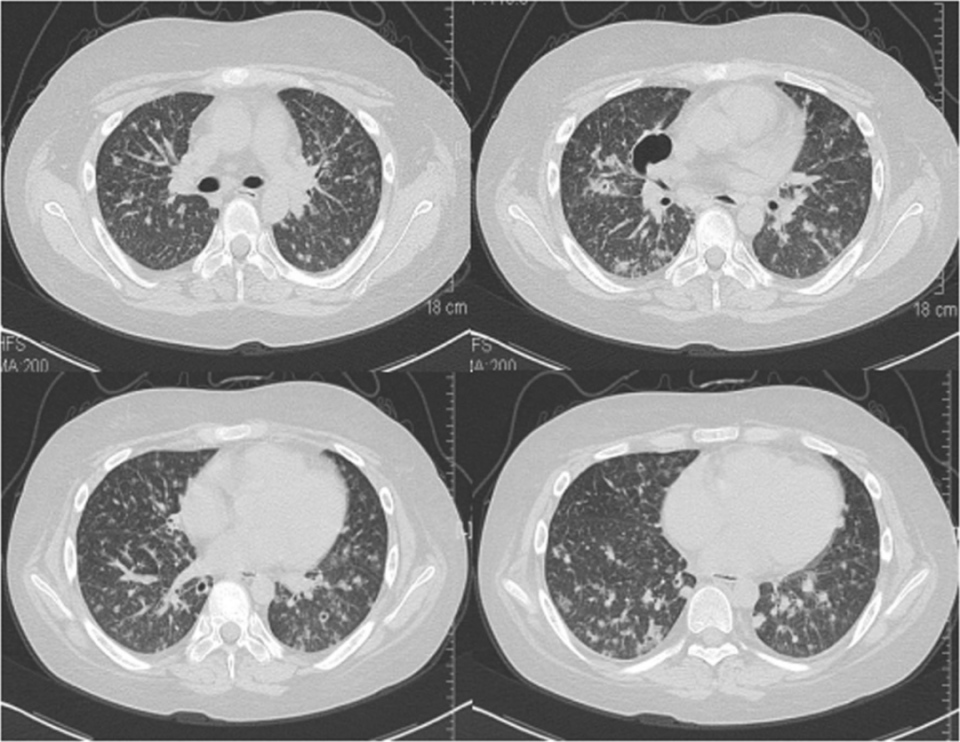

胸部计算机断层扫描(CT)显示肺部弥漫性微结节和小结节,伴有多个不同大小的空洞,右侧肺门有2.5×3.5 cm大小的局灶性厚壁空洞病变(图1)。纵隔内观察到直径<1.5 cm的小淋巴结病。腹部CT和腹部超声扫描均显示脂肪肝和左肾结石。脑部增强CT扫描未发现任何异常。

图片图1. 胸部CT显示右中叶有2.5 cm×3.5 cm大小的厚壁空洞病变,双肺均有弥漫性小结节和空洞[1]

PC的胸部影像学表现多种多样,包括结节和肿块、实变、胸腔积液等,最常见的影像学表现为单个或多个结节。PC可表现为肺内空洞,发病率为11.0%~34.6%[11,12,13],但双侧弥漫性空洞结节罕见。本病例胸部CT显示随机分布的弥漫性结节,与隐球菌气道内播散的常见影像学特征不同,与肺血源性传播一致。